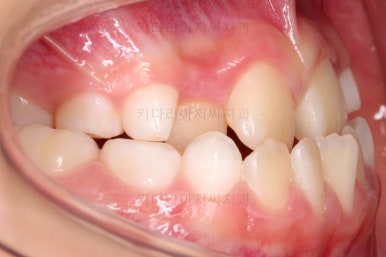

치료 종료!

총 13개월 걸려서 부산초등학생교정 위턱의 3차원적 성장과 앞니 가지런함을 다 이뤘어요.

앞니의 반대교합 뿐만 아니라 어금니 반대교합도 개선되었네요.

부산초등학생교정 전후 비교를 해보겠습니다.

부산초등학생교정 전후 모습을 보면 말 그대로 드라마틱한 변화네요.

특히 웃을 때 아랫니가 툭 튀어나와서 아랫니 위주로 보이던 미소가 완벽히 개선되어서 웃는 모습이 참 예뻐졌어요.

보호자분이 원하던 주걱턱도 개선되었고 초등학생 어린이 본인이 원하던 앞니 가지런함도 매우 좋아졌어요.